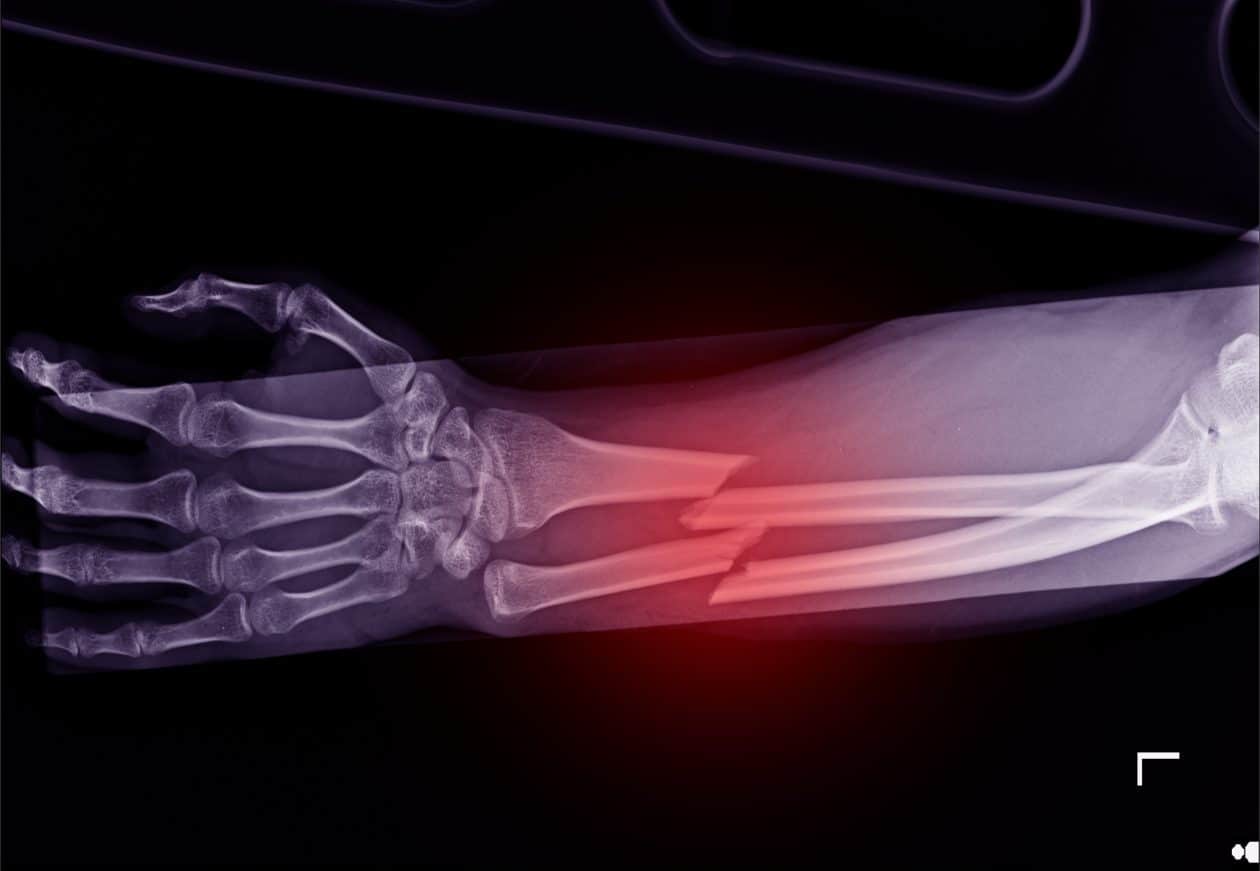

Abogados Especializados En Lesiones De Huesos Rotos De Merced